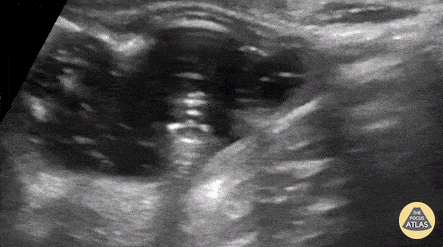

Pediatric gastrostomy replacement with injection of oral rehydration solution into gastric lumen. Cailin Frank